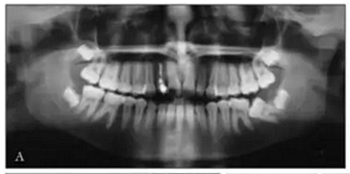

全景X線(圖3)顯示所有牙齒均存在,包括第三磨牙的牙胚。左下頜第二磨牙近中阻生。X線片顯示以前根管治療的上頜右側(cè)切牙(據(jù)報道有窩溝內(nèi)陷),對側(cè)切牙有根尖周圍病變以及窩溝內(nèi)陷的典型影像學(xué)表現(xiàn)。上頜中切牙的根部顯示先前存在的吸收。頭影測量分析顯示上頜骨和下頜骨矢狀和垂直關(guān)系正常。上頜和下頜門牙過度唇側(cè)傾斜。